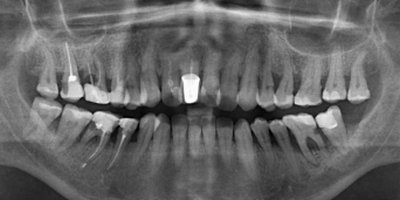

Срок восстановления костной ткани зависит от степени травматичности удаления, но как правило, от 3 - 6 месяцев. Выложите мне снимок, я вам все расскажу.